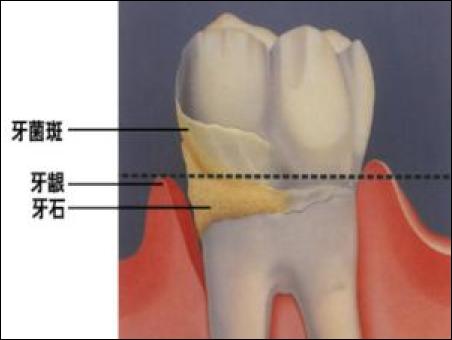

牙齒附著在牙槽骨上,外面包裹著牙齦。當牙周袋形成后,牙菌斑就會寄居于此,在牙菌斑細菌的作用下就會不斷地發(fā)炎,一方面它會侵蝕牙槽骨,讓牙槽骨慢慢地吸收;另一方面,牙齦腫脹發(fā)炎會降低牙齦與牙齒的附著力,兩種合力共同作用的結果,就是牙齒會越來越松動,直到失去固有的功能。